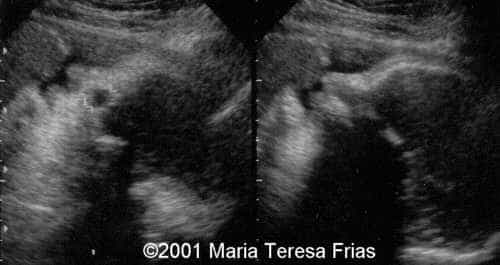

This is a case of Dacryocystocele.